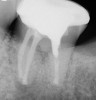

The next step in the diagnostic process was to perform objective clinical sensibility pulpal and periradicular testing to determine the etiology of the patient's chief complaint. A periapical radiograph was taken of tooth No. 18 that showed a radiolucent area present around both the mesial and distal roots(Figure 3). Tooth No. 18 tested abnormal to percussion and bite tests. Palpation, periodontal probings, and mobility were within normal limits. Tooth No. 17 had been previously extracted, and tooth No. 19 tested within normal limits to cold, percussion, palpation, bite test, mobility, and periodontal probing sensibility tests.

Preoperative periapical radiograph of tooth N o. 18.

Fig 3.